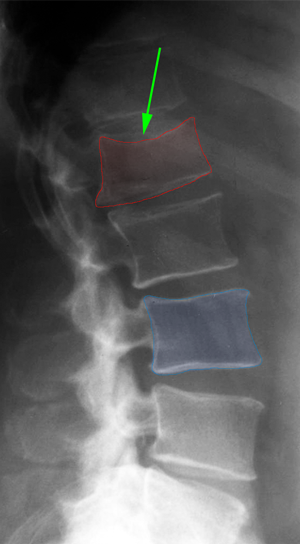

Κάταγμα Ο1 σπονδύλου (κόκκινο) με παραμόρφωση του σχήματός του. |

Οπίσθια θωρακοοσφυϊκή σπονδυλοδεσία με βίδες και ράβδους, και πεταλεκτομή, σε ασθενή με ασταθές κάταγμα Ο1 σπονδύλου. |